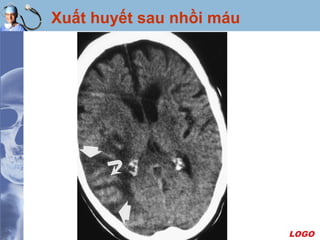

Xuất huyết sau nhồi máu

Xác định thời gian nhồi máu

 Fogging effect: hiện tượng đồng đậm độ vùng nhồi máu

 Một số trường hợp có hiện tượng tăng quang do xuất

huyết trong vùng nhồi máu vào sau ngày thứ ba.